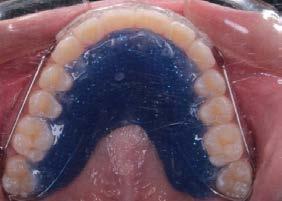

Por lo que se propone procedimiento quirúrgico con la evidente comunicación oroantral al realizar las extracciones de los órganos dentales involucrados. Previa asepsia y antisepsia, colocación de campos estériles, extracción de segundo y tercer molar superior derecho e incisión envolvente con descarga mesial (Figura 3), rotación y afronte mediante puntos simples de la bola adiposa de Bichat para el cierre de la comunicación oroantral (Figura 4), farmacoterapia con base en amoxicilina con ácido clavulánico. Una semana después refiere no presentar rinorrea y mejoría al 100% de la obstrucción. Posterior a 6 meses de evolución clínica (Figura 5) y radiográficamente (Figura 6), no se observa comunicación oroantral o paso de líquidos de la cavidad oral a la cavidad nasal.

Figura 1. Fotografía oclusal.

Figura 5. Fotografía oclusal de 6 meses de evolución.